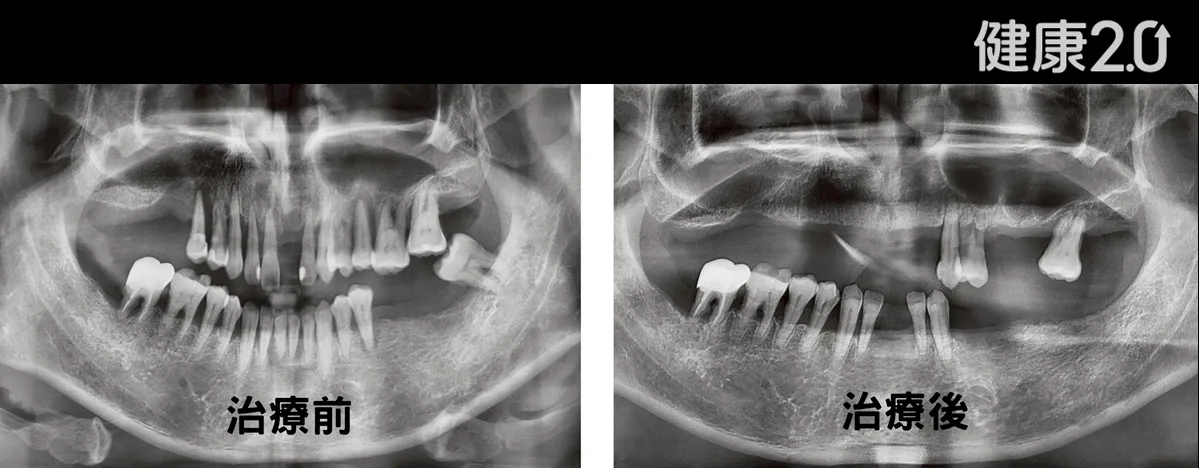

吳欣哲表示,牙周病是「沉默的破壞者」,初期症狀如牙齦流血、腫脹容易被忽視,但細菌會持續侵蝕齒槽骨,甚至經由血液循環影響全身。臨床案例中,一名50多歲男性早年因忙碌忽視牙周病,直到牙齦腫痛與掉牙造成咀嚼困難才就醫求診,經檢查發現牙齒動搖度高,懷疑患者代謝系統異常,進一步轉診發現患者血糖嚴重異常,飯後血糖竟高達410mg/dL(正常飯後<200mg/dL),顯示胰島素功能失調。

吳欣哲指出,研究顯示,血糖控制不佳者罹患牙周病風險增加2至3倍,若再加上吸菸習慣,風險更可達4.6倍。該患者在同步接受糖尿病與牙周治療後,不僅成功保住11顆牙,並在牙周病療程結束後進行假牙重建,恢復正常咀嚼功能。經過5年追蹤,他的糖化血色素穩定控制在7%以下,牙齒狀況也良好,顯示跨科整合治療對提升預後具有關鍵作用。